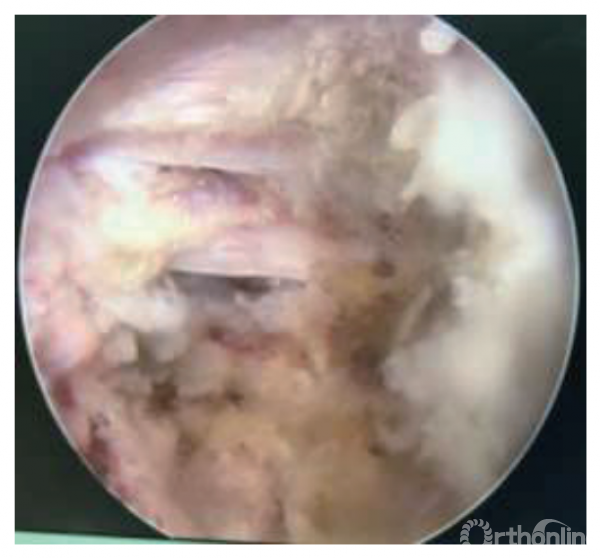

(4)镜下切除突出的椎间盘:安装椎间孔镜的光源、视频成像系统和水冲洗系统,调节工作套筒不同的角度,显示突出的椎间盘,通过不同型号和角度的髓核钳取出突出的髓核组织,用镜下剪刀去除部分黄韧带,扩大神经根管。用射频刀头对镜下的出血点止血,对纤维环和髓核组织进行固化成型。向上、下探查神经根的走行,明确神经根周围致压物是否完全清除。对于脱出或者游离型椎间盘突出的患者,在结束手术前需要反复检查神经根周围有无残留的髓核组织(图2)。术中通过直腿抬高实验来观察神经根的滑动,明确患者的根性疼痛是否完全消失。

图注:A组为伴有高髂嵴的L5/S1椎间盘突出症患者,采用侧方入路经皮椎间孔镜下椎间盘切除治疗

图2|A组椎间孔镜下可见神经根周围致压物已经被清除,神经根松弛